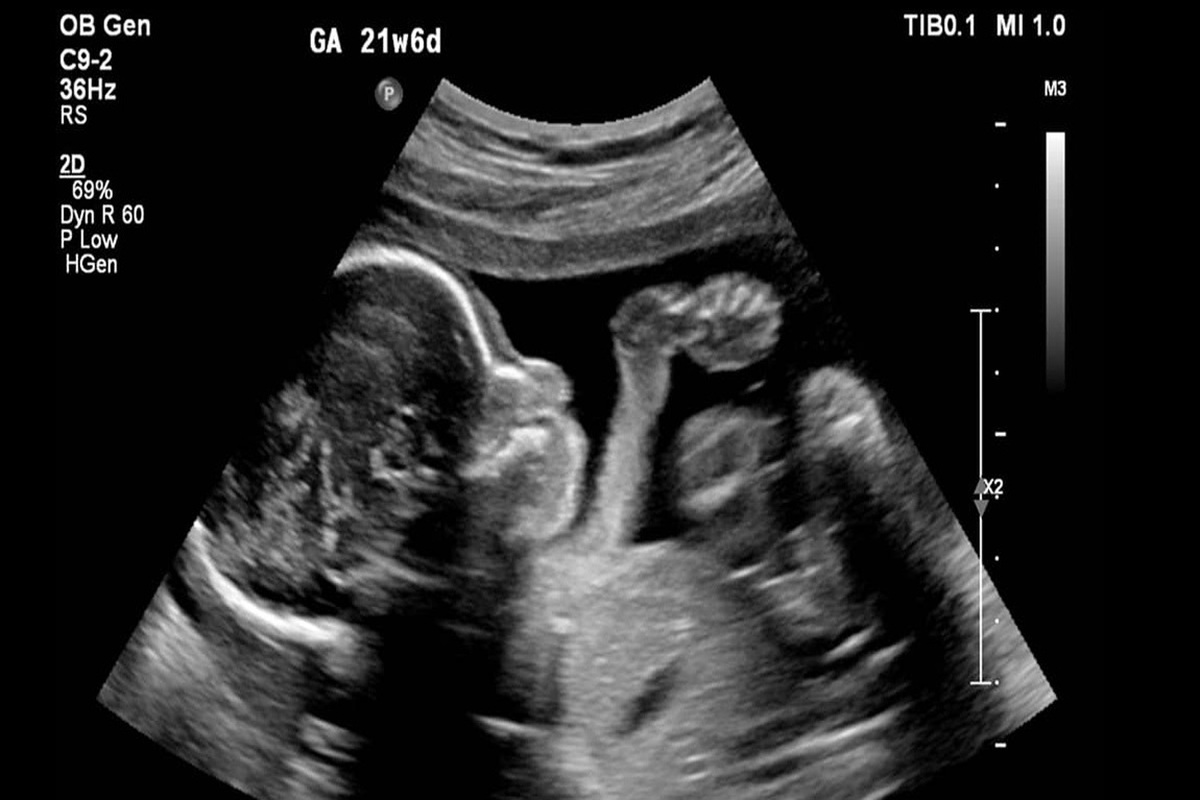

وی درباره راه‌اندازی سامانه ملی باروری سالم، گفت: سامانه ملی باروری سالم ابلاغ شد. قرار است در قالب این سامانه از زمانی که تست حاملگی خانمی مثبت می‌شود و جنینی تشکیل می‌شود تا زمانیکه متولد می‌شود، در این سامانه ثبت می‌شود. به تدریج آزمایشگاه‌ها، پزشکان متخصصی و ... به این سامانه وصل می‌شوند و اگر احیانا نیاز به غربالگری باشد، در این سامانه ثبت می‌شود و اگر نیاز به سقط درمانی باشد، در این سامانه ثبت می‌شود تا بتوانیم یک جنینی را که تشکیل می‌شود تا زمان تولدش ردیابی کنیم تا این جنین‌ها از دست نروند و بتوانند به جمعیت سالم کشور اضافه شوند.